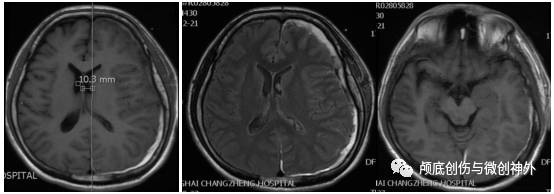

头颅MRI平扫:

1.左侧额颞颞亚急性硬膜下血肿;

2.颅内高压。

3. 影像学提示:中线移位大于1cm,左侧颞叶沟回压迫脑干,左侧顶部皮层脑沟变窄,脑回增宽,回流静脉曲张。

1. 正确掌握手术指证是关键,侯主任领导在团队根据当地医院钻孔引流术后病情未好转、CT和MRI显示占位效应明显,再次采取开颅手术,手术指证正确;